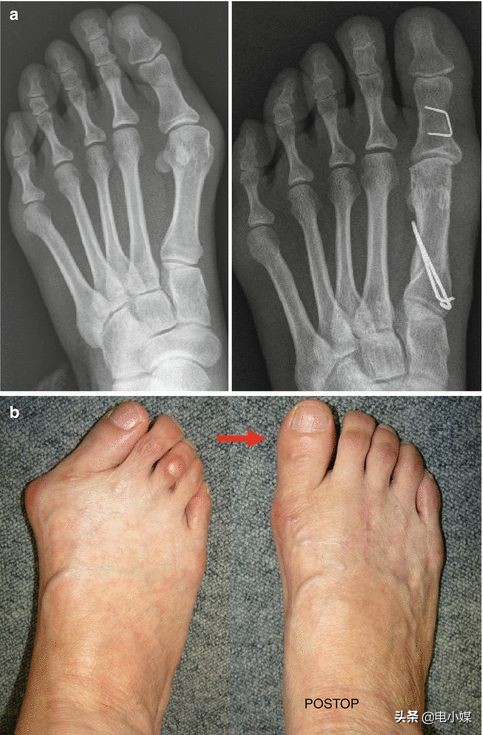

对于脚本身,踮脚姿势增加前脚掌压力(特别是拇趾周围),加上很多尖鞋头挤住脚趾,会改变足弓高度,使拇外翻风险升高1~2倍,还可能导致足底筋膜炎及骨骼变形[1, 8, 9]。

左侧为拇外翻X线片及足部照片,右侧为术后丨参考文献[10]